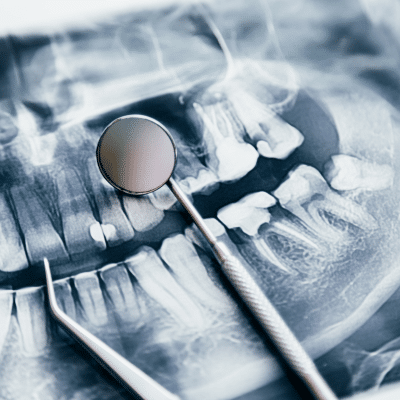

Explore posts on topics including preventive dentistry, cosmetic enhancements, restorative solutions, implants, and oral wellness tips. You’ll also find practical guidance for at-home care, managing dental anxiety, and staying current with the latest dental technology and treatment options.